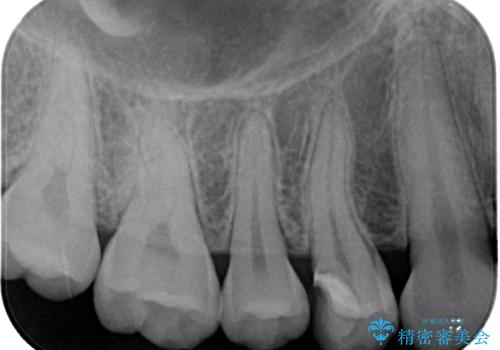

フロスの引っ掛かりやレントゲン像から、CRを除去し、虫歯を徹底的に除去し、精度の高いセラミックインレーにて修復することとしました。

虫歯が神経に近接している可能性があるため、念のためラバーダムをして虫歯の除去を行いました。

レントゲン像から、隙間のない精度の高い詰め物が入っていることが確認できます。